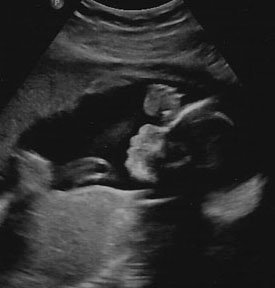

Беременность 22 недели мальчик

Беременность 22 недели мальчик 115 фото